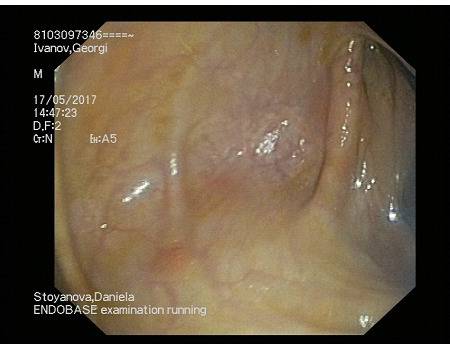

Нека погледнем следващата снимка.Тя е след ЗРХТ – при седемгодишен тежък улцерозен колит.За публикуването и ни е дадено разрешение – като личните данни -по ЕГН ,не са верни спрямо оригинала: